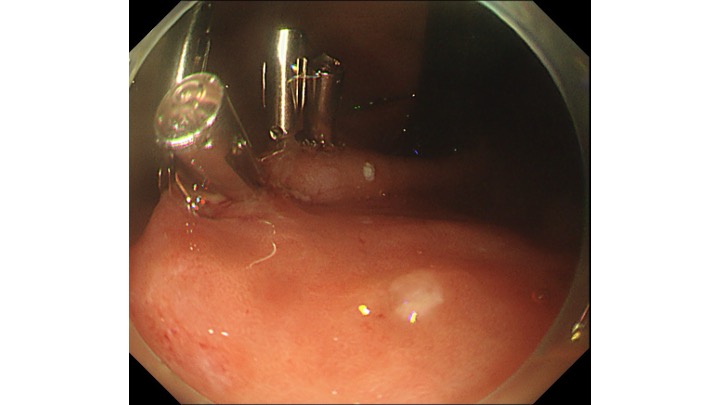

電気メスでマーキングをして、わずか8分で内視鏡治療終了しております。

内視鏡治療エキスパートのクリニックであれば、胃癌の内視鏡治療(ESD)は入院せず、日帰り治療の時代が到来したと考えております。